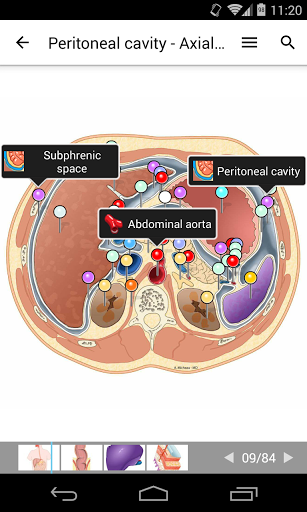

e-Anatomy tiene más de 26 000 imágenes que contienen series de imágenes en vistas axiales, coronales y sagitales, así como radiografías, angiografías, imágenes de disección, gráficos anatómicos e ilustraciones. Todas las imágenes médicas fueron etiquetadas cuidadosamente, más de 967 000 etiquetas disponibles en 12 idiomas, incluida la Terminologia Anatomica latina.

- Desplácese por los conjuntos de imágenes arrastrando el dedo

- Acerque y aleje el zoom

- Toque las etiquetas para mostrar las estructuras anatómicas

- Seleccione las etiquetas anatómicas por categoría